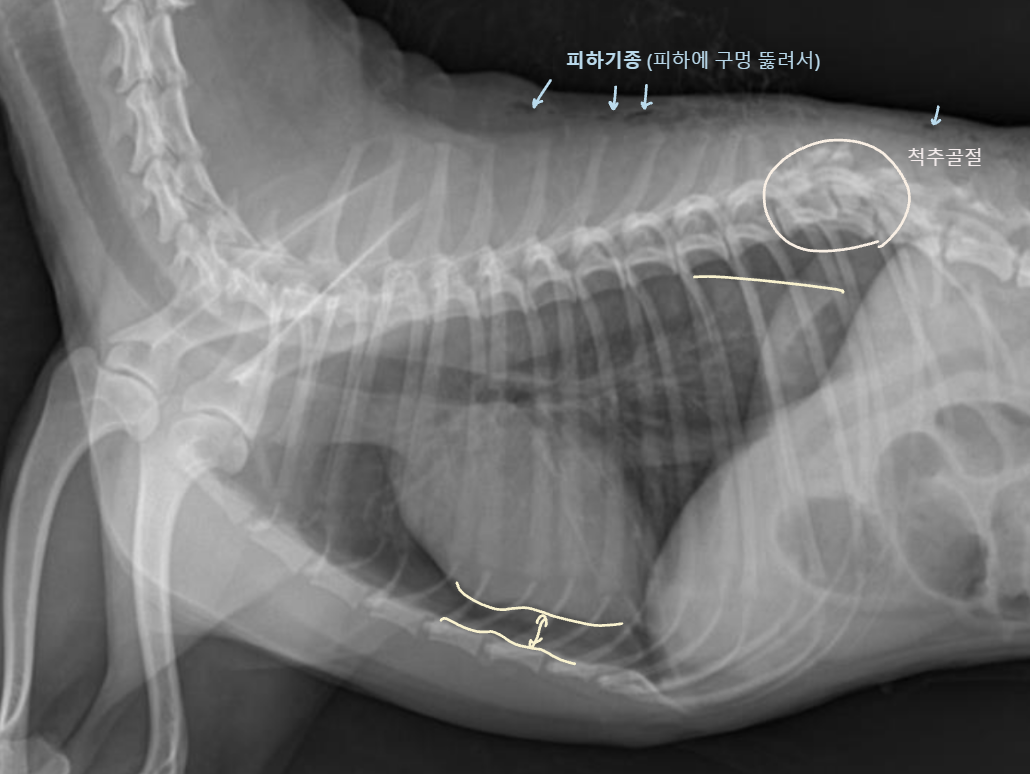

Tracheal rupture

4. Pleural Space

Pleural effusion (흉수)Pneumothorax (기흉)

흉강(pleural cavity)에 물이 찬 것

(폐에 차면 → 폐수종)

흉강에 공기가 찬 것

(폐에 차면 → 폐기종)

Radiographic signs

interlobar fissure 두껍게 관찰되고,

흉벽이 떨어져 나간 것처럼 보임

심장이 떠 있고, 폐가 쪼그라듦

- Interlobar fissure widening

- Lung retraction

- Pleural wall thickening

- Scallop sign

- Cardiac effacement

- Blunt angle

- Retraction of pleural surface

- Collapsed lung (→ opacity 증가)